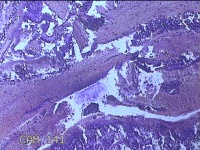

性别

女

年龄

44岁

临床诊断

子宫异常出血;子宫肌瘤;子宫内膜息肉

一般病史

阴道流血1月。

标本名称

宫颈管内膜

大体所见

纱布一块,内有灰白暗红色不规则碎组织1.5x1x0.2cm一堆。

图1